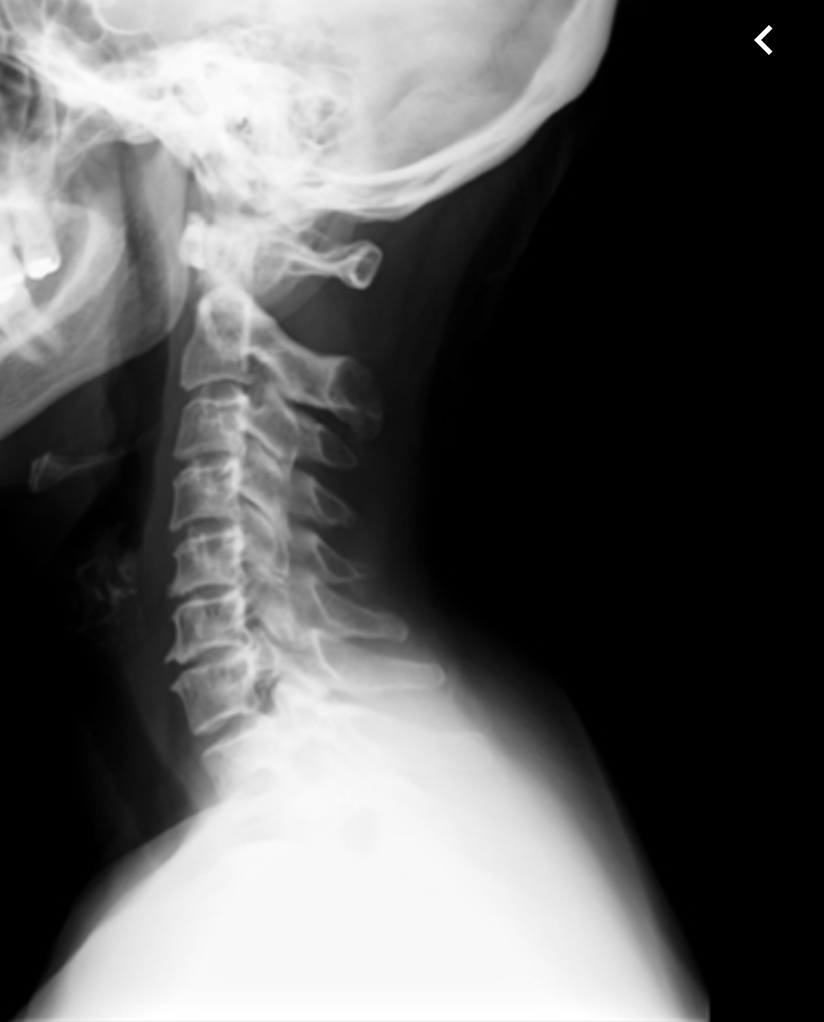

Cite aspectos que devem ser descritos na radiografia cervical.

Descreva a anatomia de superfície do pescoço.